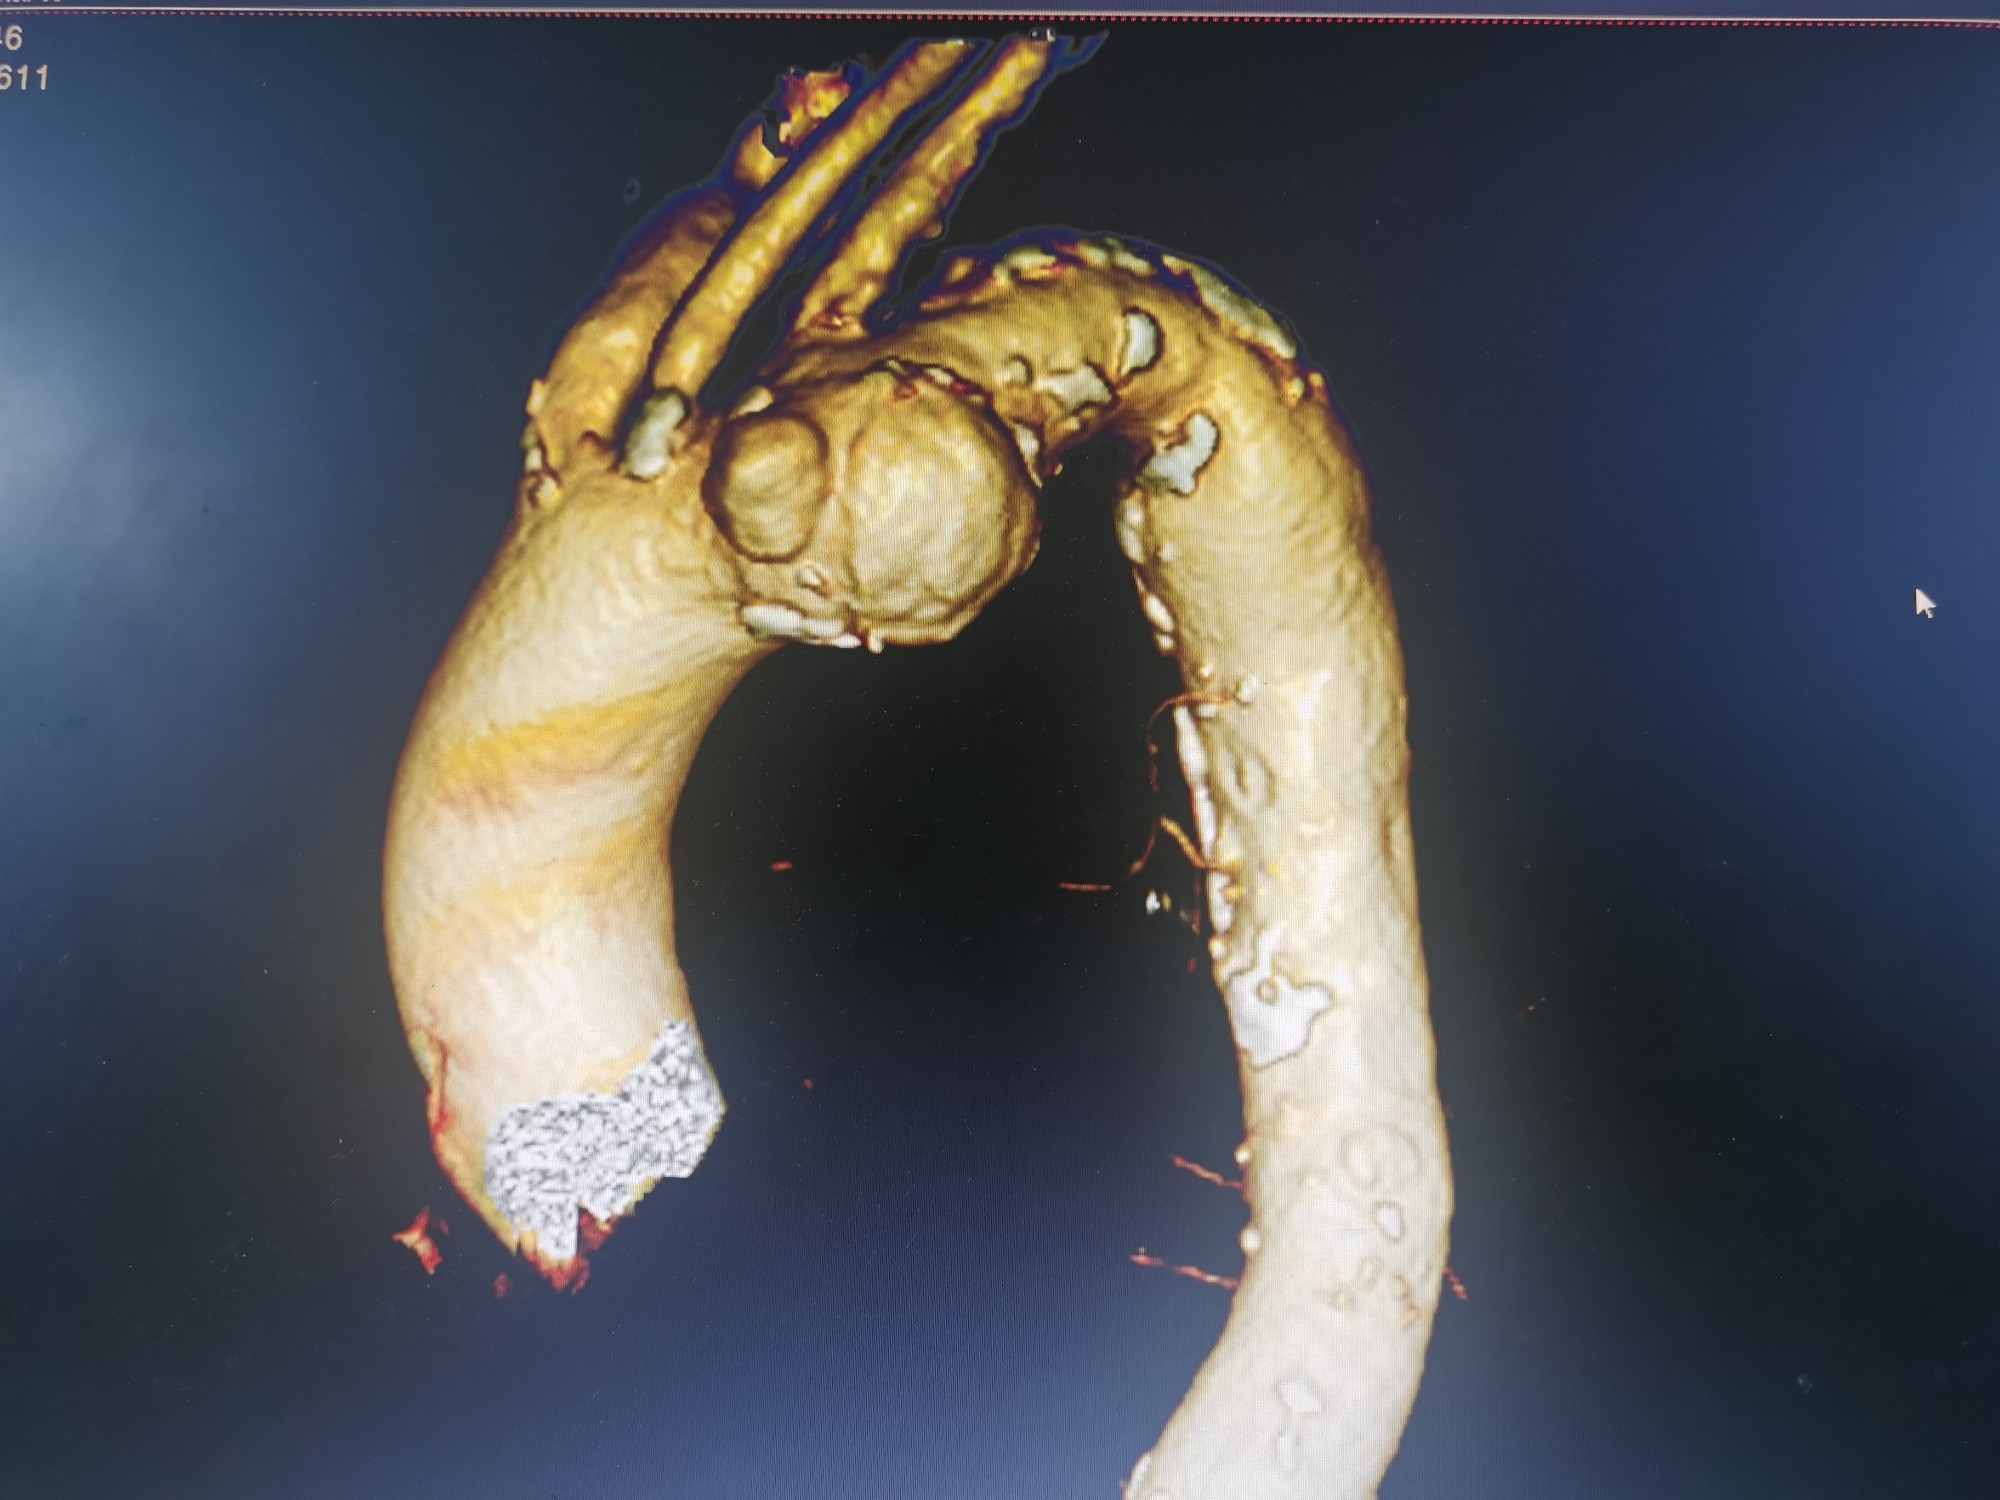

术前CTA三维